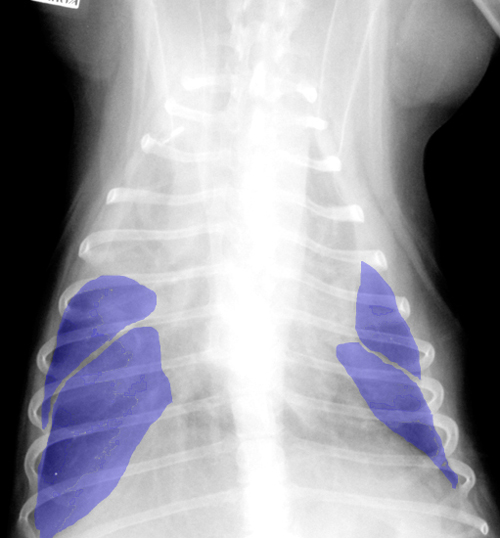

Симптомы и причины скопления воды в легких